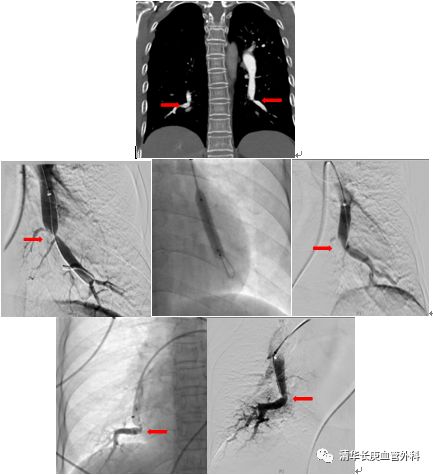

北京清华长庚医院血管外科团队在吴巍巍主任的带领下,联合多科讨论后决定采用肺动脉球囊扩张成形术治疗通过右侧股静脉入路,选择进入患者左侧肺动脉基底段狭窄部位,完成肺动脉球囊成形术,球囊扩张后肺动脉形态改善。患者术后在监护病房视察一天后顺利返回普通病房,患者恢复顺利。一周后再次行右侧肺动脉基底段球囊扩张。患者术后6分钟步行距离明显提高,术后2天即可行走450m,肺动脉压力由术前82mmHg降至8mmHg6 。患者顺利出院,由于双侧肺动脉病变广泛,此后还将密切随诊,择期再次行其余部位的肺动脉腔内治疗。

双侧肺动脉基地段狭窄,球囊扩张前后对比